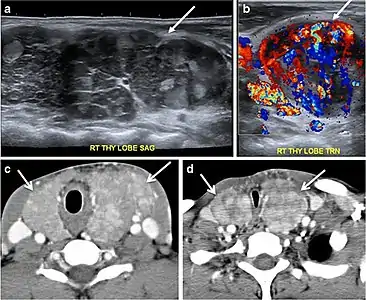

Goiter

A goiter is an abnormal thyroid gland proliferation that manifests as multi-nodular, uni-nodular, or non-nodular diffuse glandular enlargement. A goiter is formed of solid matrix, colloid cysts, blood products, calcification, and fibrosis, and this heterogeneity may lead to variable appearances on a CT scan (Figs. 13, 1414 and and15)15). The US is more sensitive in evaluating thyroid nodules within a goiter; however, a symptomatic goiter may require surgical treatment with total thyroidectomy, and in this case CT plays an additional role in preoperative evaluation. Specific aspects for examination on a CT scan during the preoperative evaluation for goiter include extension, mass effect, and suspicious features of malignancy.[1]

Fig. 13. A 27-year-old female patient known to have goiter. a, b Axial and sagittal enhanced CT scan images of the neck demonstrate a heterogeneously enhancing, enlarged thyroid gland with scattered calcifications (white arrow), cystic changes, and substantial retro-sternal extension (black asterisks). No lymphadenopathy or substantial airway narrowing.[1]

Fig. 14. A 19-year-old male patient known to have multi-nodular goiter and FNA, showing underlying Hashimoto's thyroiditis. a, b Sagittal and transverse greyscale and colour Doppler ultrasound of the neck demonstrate a hypoechoic enlarged right thyroid lobe with small hyperechoic regenerative nodules and marked hypervascularity (white arrows). c, d Enhanced axial CT scan images of the neck demonstrate a heterogeneously enhancing and enlarged thyroid gland, left more than right lobe, and the trachea is markedly narrowed.[1]

Malignancy can coexist within the goiter and a CT scan may give a clue if there are abnormal cervical lymph nodes and/or signs of invasion. Retrosternal extension (Fig. 15) could affect the surgical approach, as a lower extent may require a partial or total sternotomy to facilitate complete resection. Therefore, the distance of the retrosternal extent from the sternal notch should be measured on a sagittal image.[1]

The interpreting radiologist should describe the mass effect, detailing its degree and direction of displacement of central structures, including the trachea, oesophagus, larynx, and pharynx. Attention should be directed to the upper extent of the goiter and structures immediately surrounding the thyroid gland, including the neuro-vascular structures, retropharyngeal space, and pre-vertebral space. The reporting radiologist should evaluate the vocal cords for symmetry and signs of vocal cord palsy.[1]